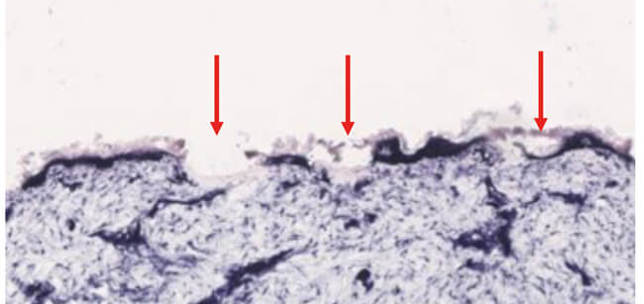

Aesthetic Medicine , Dermatology

Skin biorevitalisation with hyaluronic acid